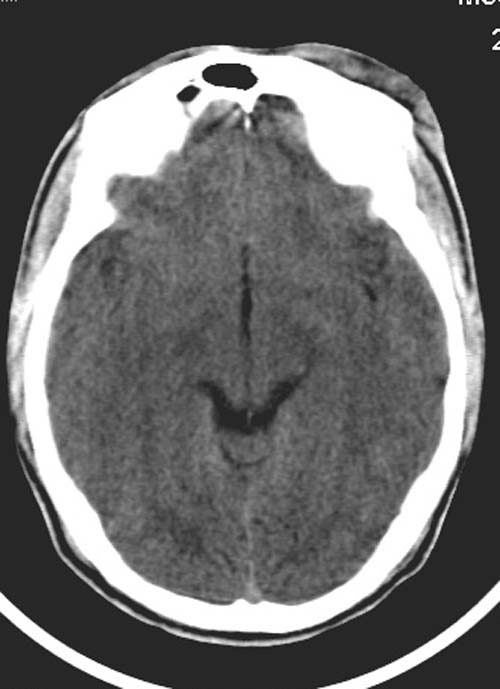

患者,男,26岁。头面部外伤半小时。

颅内未见明显异常.

左额部软组织肿胀

左额部软组织肿胀,还有别的事吗?

左额部软组织肿胀  ,别的?

左额部软组织损伤,左泪囊损伤

复查一下吧,左侧颞叶两个层面都有异常密度灶。不知道是伪影不。

左侧眶部软组织肿胀,楼主是不是考虑有静脉窦血栓?复查或增强扫描。